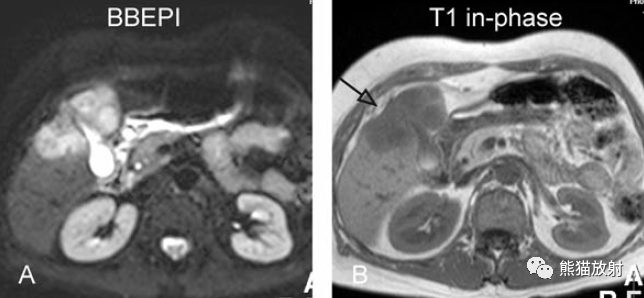

T2壓脂(T2 fatsat):膽囊窩內(nèi)膽囊癌病變較肝臟為高信號(hào),病變頂部向肝內(nèi)擴(kuò)展;

T1同相位(T1 in-phase):膽囊癌病變較肝臟為低信號(hào);

增強(qiáng)動(dòng)脈期(ART):不均質(zhì)強(qiáng)化;

延遲期(DEL):部分廓清,部分持續(xù)強(qiáng)化。

膽囊癌。A~D圖:上方層面,表現(xiàn)如上所述,形成腫物侵及肝臟。E、F圖:下方層面示膽囊壁不規(guī)則增厚,明顯不均質(zhì)強(qiáng)化。